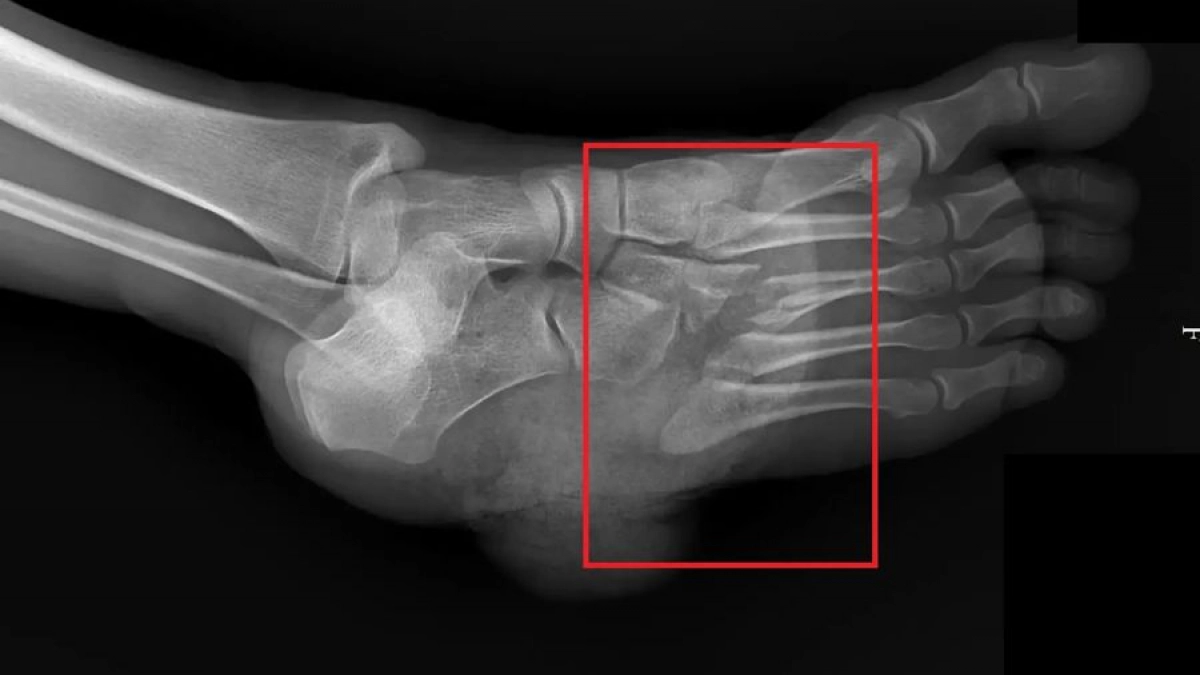

Пострадавшую на скорой доставили в травматологическое отделение. После осмотра и рентгена врачи решили, что медлить нельзя, и пациентку сразу отвезли в операционную. Хирурги занялись восстановлением поврежденных костей и сухожилий стопы.

"Работа с острыми и тяжелыми инструментами требует особой осторожности… В данном случае, оперативное реагирование позволило сохранить стопу пациентки", – сообщил заведующий травматологическим отделением Алексей Доманов, напомнив о важности соблюдения техники безопасности при любых домашних работах.